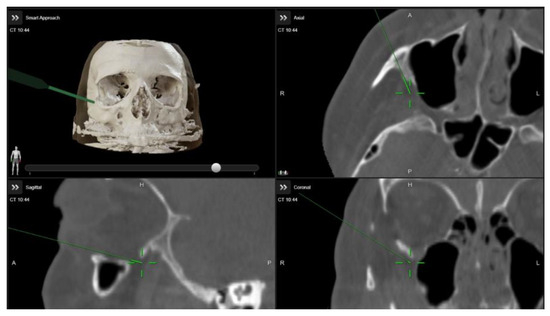

A multidisciplinary surgical approach was employed, involving craniomaxillofacial surgery, otolaryngology, and ophthalmology services. The procedure was planned to use computed tomography (CT) imaging with navigation markers. The images were processed using BrainLab® software (Brainlab Elements, 2024 release), enabling precise multiplanar and three-dimensional (3D) anatomical assessment (Figure 3 and Video S1). Different orbital wall areas were color-coded to facilitate intraoperative identification.

Figure 3.

Intraoperative images demonstrating the use of image-guided navigation during orbital decompression surgery. The green arrow indicates the navigation pointer within the Brainlab system.

Image-guided surgery (IGS) has revolutionized orbital procedures by enhancing surgical precision and minimizing complications. At our institution, intraoperative navigation (BrainLab®) and intraoperative cone beam computed tomography (Loop-X®) have been adapted for orbital decompression, integrating preoperative imaging data with real-time intraoperative navigation. This system integrates preoperative imaging data, such as magnetic resonance imaging (MRI) or computed tomography (CT) scans, with real-time intraoperative feedback and allows surgeons to visualize the exact location of instruments relative to critical anatomical structures, optimizing surgical planning and execution [13].

Preoperative high-resolution imaging is used to generate a detailed three-dimensional (3D) model of the surgical site, which is uploaded to the Brainlab platform. Before surgery, we plan the surgical objective, designing the osteotomies and the resection of the orbital walls to achieve the final volumetric outcome. During surgery, specialized instruments equipped with sensors or optical markers interact with the system, allowing real-time tracking of their position and orientation relative to the preoperative model. This enables precise localization of surgical tools in relation to critical anatomical structures. By providing continuous feedback on instrument proximity to delicate regions, the system facilitates accurate decision-making and intraoperative adjustments, enhancing precision, optimizing surgical planning, and potentially reducing operative time and complications.